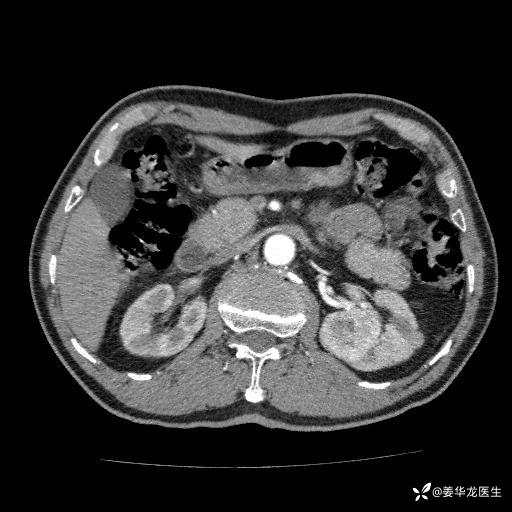

左肾中心型肾门部肿瘤39mm×34mm×36mm,右肾GFR25ml/min,部分切还是全切?

患者75岁老年男性,体重50kg,无高血压、肾病、糖尿病等基础病,检查发现左肾中心型肾门部肿瘤,右肾GFR只有25ml,无肉眼血尿,无镜下血尿。入院验血常规检查均正常,包括肾功能,肌酐102.7umol/L.

二、左肾肿瘤与左肾集合系、左肾动静脉关系密切,左肾部分切除术可行吗?成功率有多大?成功部分切后,肾功能还有多少?